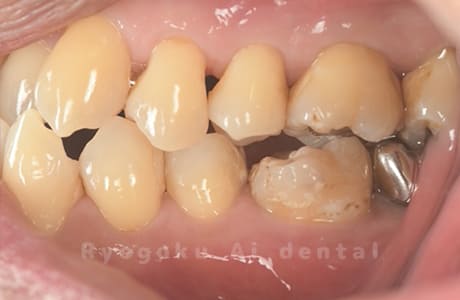

Case19

-

- 原因

- 重度カリエス、インレー・クラウン二次カリエス

- 治療内容

- 47:自家歯牙移植 46:ダイレクトボンディング 45:ジルコニアクラウン

- 治療費用

- 約456,500円

虫歯が大きく、保存困難な右下7番を埋まっている親知らずを再利用しました。経過も良好です。

<リスク・副作用>

治療後、痛みや違和感、出血、腫れなどが出る事があります。喫煙者、糖尿病などの方の場合、歯が生着しない場合があります。